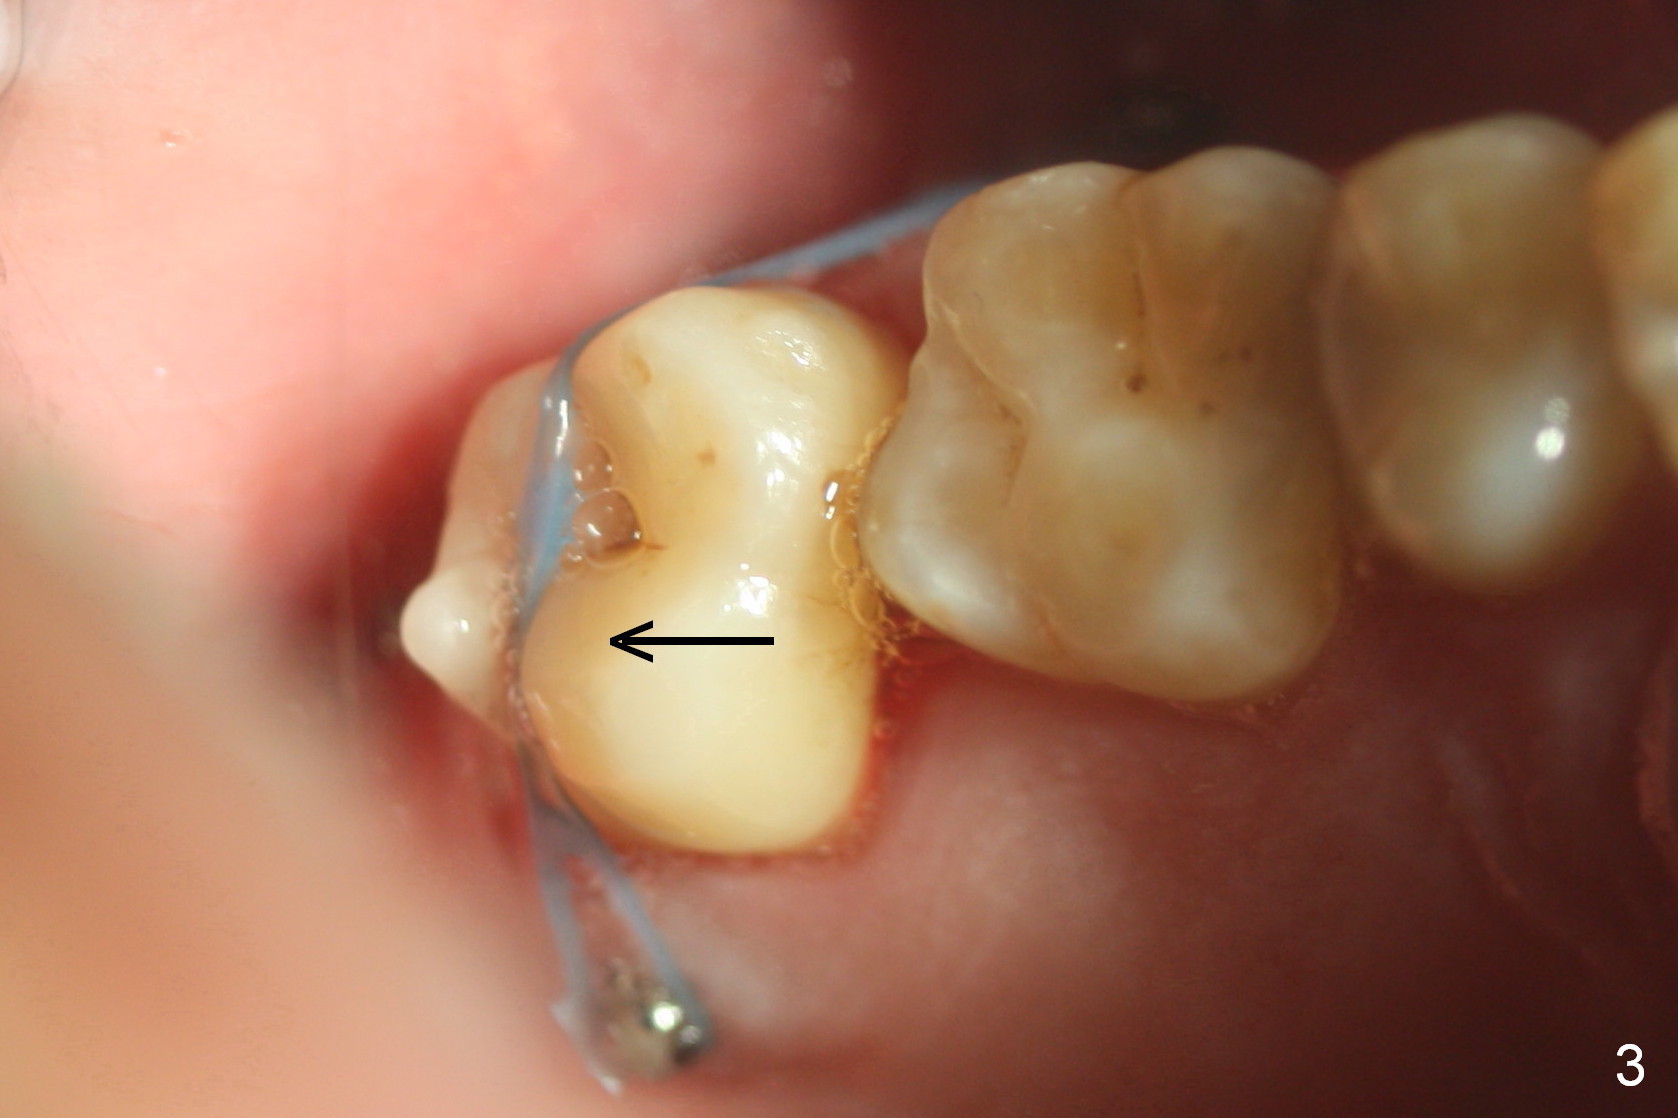

A 50-year-old man has lost the tooth #18 for 10 years; the opposing tooth (#15) has been supraerupted in the last 6 years (Fig.1,2). Mini-implants are placed to intrude the tooth #15 (Fig.2 arrow), instead leading to distalization in 4 months (Fig.3 arrow). Segmental orthodontic appliances are placed with noncompliance. Five months post implant placement at #18, a provisional (Fig.5 P) is fabricated with intentional supraocclusion. In 4 months, the marginal ridges of the teeth #14 and 15 are at the same level (Fig.4). To prevent the 2nd molar from distalization, keep the third molar if present.